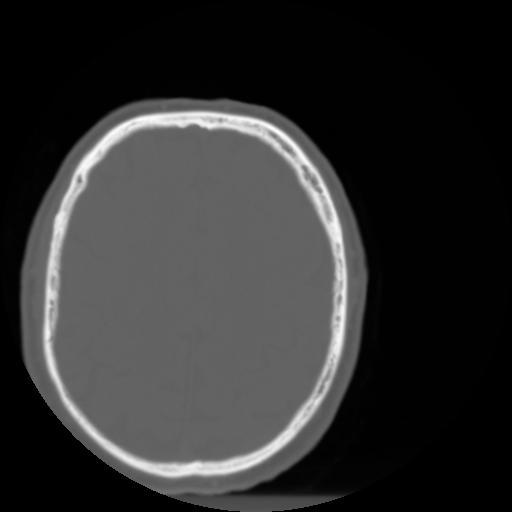

3 CEREBRO,,Axial,3.0,CEREBRO,,